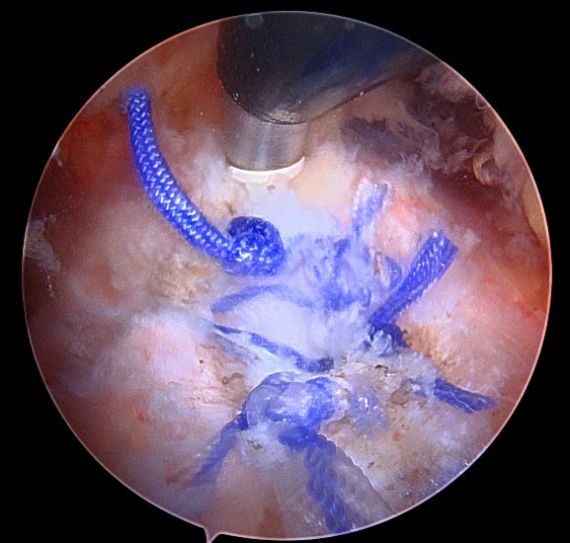

Hip arthroscopy, also referred to as "keyhole" or minimally invasive hip surgery, is typically necessary for hip pain that does not improve with conservative treatment. Small incisions are made only big enough to place a small video camera and specialized instruments into the hip joint, trochanteric space, and/or ischial space to clearly diagnose and treat hip pathology.

Types of Repair

Click on a hip condition below to see the repair.